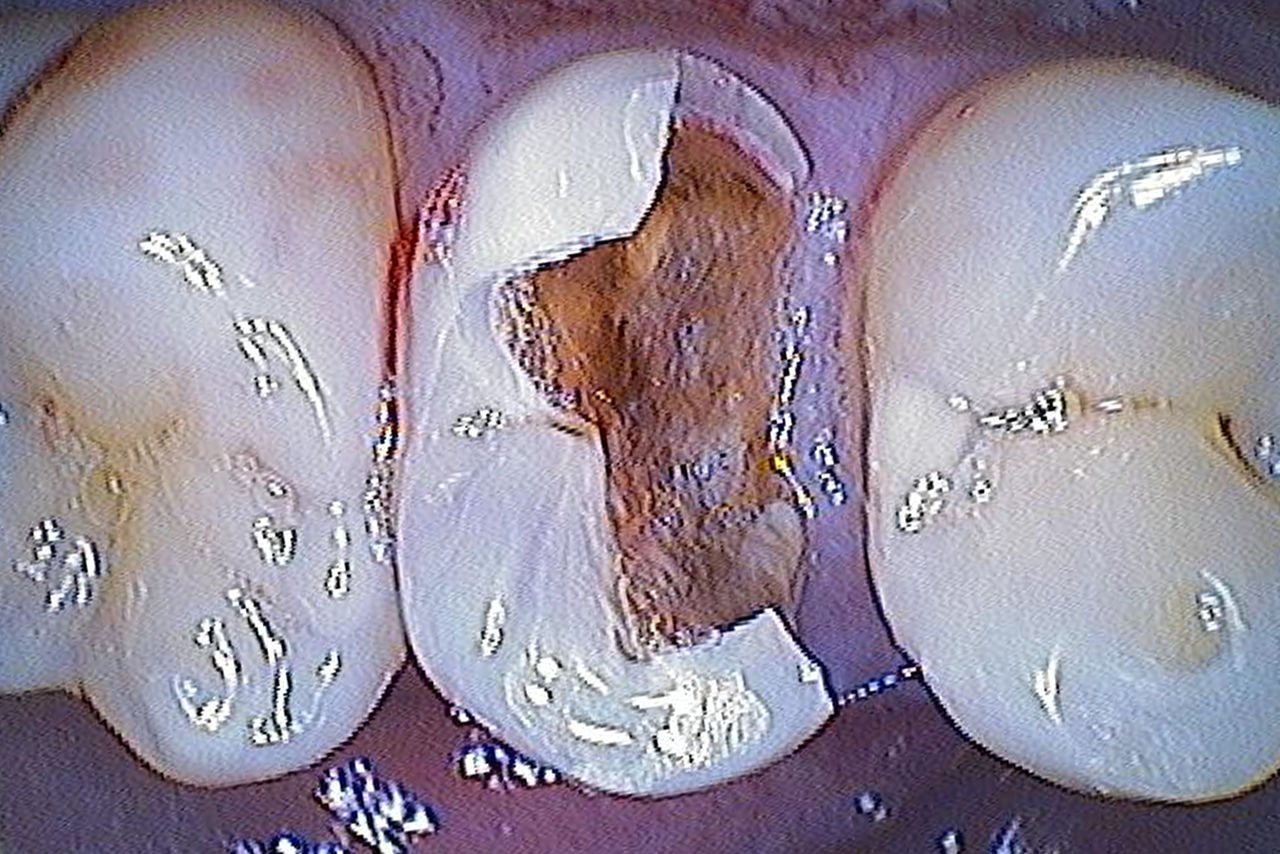

Antes: El primer molar superior se había restaurado con un relleno de composite extenso pero insuficiente que ya mostraba fracturas visibles.

Antes: Restauración de cerámica fracturada hecha de vitrocerámica reforzada con leucita después de un tiempo de servicio clínico de 12 años.

Antes: Insuficiencia grande del relleno de composite en el diente 16 con grietas marginales distales en la cresta, una grieta en la pared lingual y caries recurrente distal.

Antes: El diente 26 presenta caries y una restauración de composite directa defectuosa.